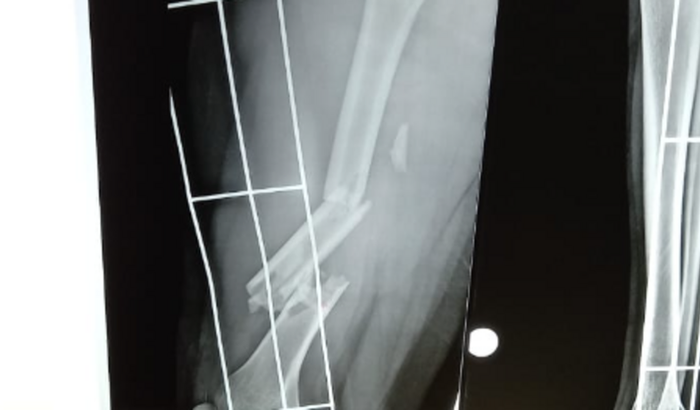

Meu nome é Amanda Laiz, fiz essa vaquinha para arrecadar o valor de 20.000,00 R$ para realizar minha cirurgia do fêmur que foi quebrado em dois lugares após um acidente de moto, quebrei também a clavícula, e quebrei um dedo, esse valor vai me ajudar com as cirurgias cabiveis